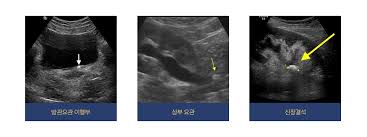

2. 초음파

- 초음파는 엑스레이와 달리 방사선을 쏘이지 않으므로 건강상에 문제가 되지는 않습니다. 하지만 비용이 엑스레이보다는 비싸기 때문에 치료를 위하여 보다 정확한 위치를 파악하고, 그 사이즈(돌의 크기)를 측정하기 위한 작업입니다.